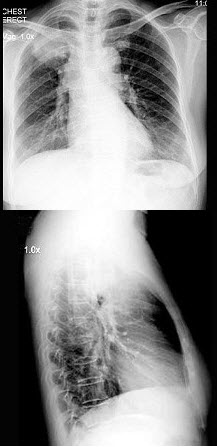

21、单项选择题

女,63岁,痰中带血2天,不咳嗽、发热,X线检查如图,最可能的诊断是()

A.右上肺结核

B.右上肺炎症

C.右上肺不张

D.右上肺癌

E.右上肺错构瘤